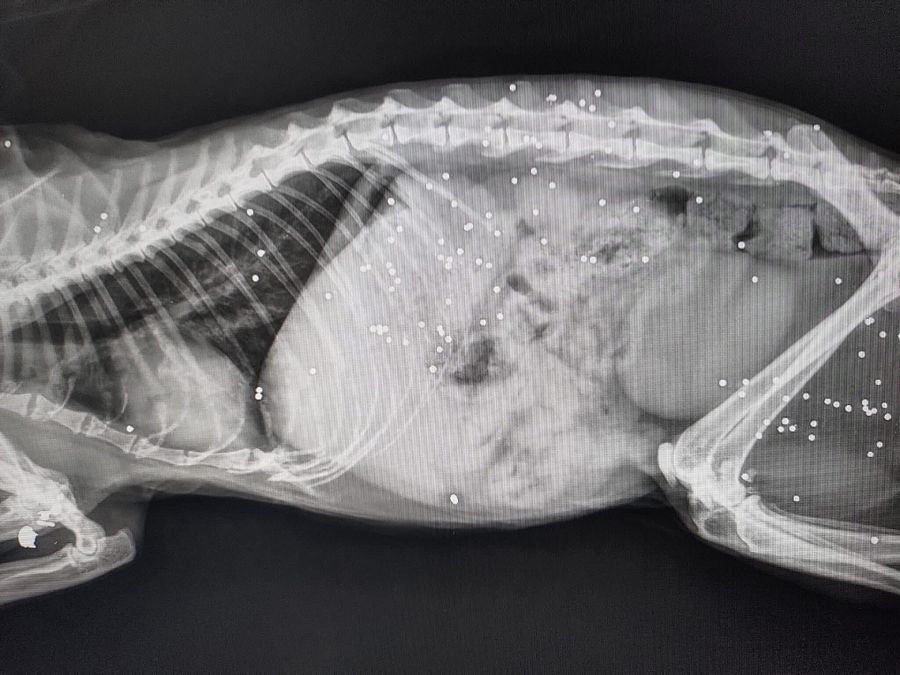

Una delle due ha una zampa gravemente compromessa spiega l'associazione che ha subito avvertito due veterinari della zona che si sono messi immediatamente al lavoro, gli hanno già somministrato le medicine per alleviare il loro dolore. "Stanno cercando una protesi speciale che permetta alle gattine di tornare a vivere alla normalità". "La situazione di una gatta è più critica: oltre alla zampa seriamente danneggiata presenta numerosi pallini di piombo nel corpo. I veterinari stanno valutando con grande attenzione come intervenire per salvarle la vita".